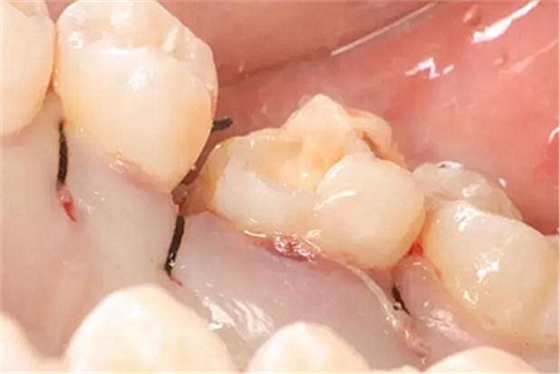

改良垂直褥式縫合關(guān)閉傷口,傷口無明顯滲血,高嵌體預(yù)備完畢后,硅橡膠取模,見邊緣清晰。灌注模型,模型上3MZ350XT分層堆塑高嵌體。

一周后拆除縫線,試戴高嵌體,試戴合適后雙固化粘結(jié)。調(diào)合,拋光。